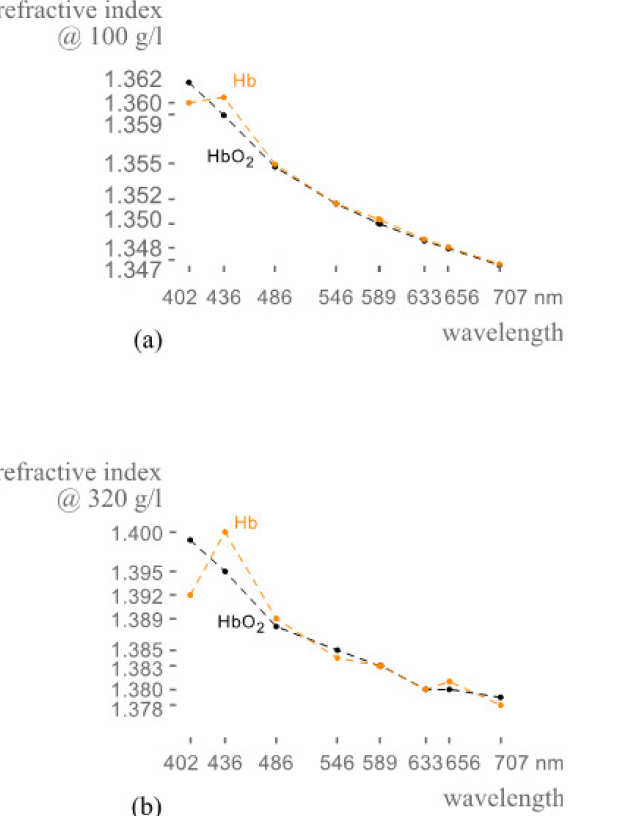

O. Sydoruk (in collaboration with Erlangen-Nuremberg University and Saratov University)

Because the refractive index of hemoglobin in the visible range is sensitive to the hemoglobin concentration, optical investigations of hemoglobin are important for medical diagnostics and treatment. Direct measurements of the refractive index are, however, challenging; few such measurements have previously been reported, especially in a wide wavelength range. We directly measured the refractive index of human deoxygenated and oxygenated hemoglobin for nine wavelengths between 400 and 700 nm for the hemoglobin concentrations up to 140 gl−1. We analyzed the results and suggested a set of model functions to calculate the refractive index depending on the concentration. At all wavelengths, the measured values of the refractive index depended on the concentration linearly. Analyzing the slope of the lines, we determined the specific refraction increments, derived a set of model functions for the refractive index depending on the concentration, and compared our results with those available in the literature. Based on the model functions, we further calculated the refractive index at the physiological concentration within the erythrocytes of 320 gl−1. The results can be used to calculate the refractive index in the visible range for arbitrary concentrations provided that the refractive indices depend on the concentration linearly.

|

|---|

| Refractive index of oxygenated and deoxygenated haemoglobin (a) measured and (b) calculated at different haemoglobin concentrations |